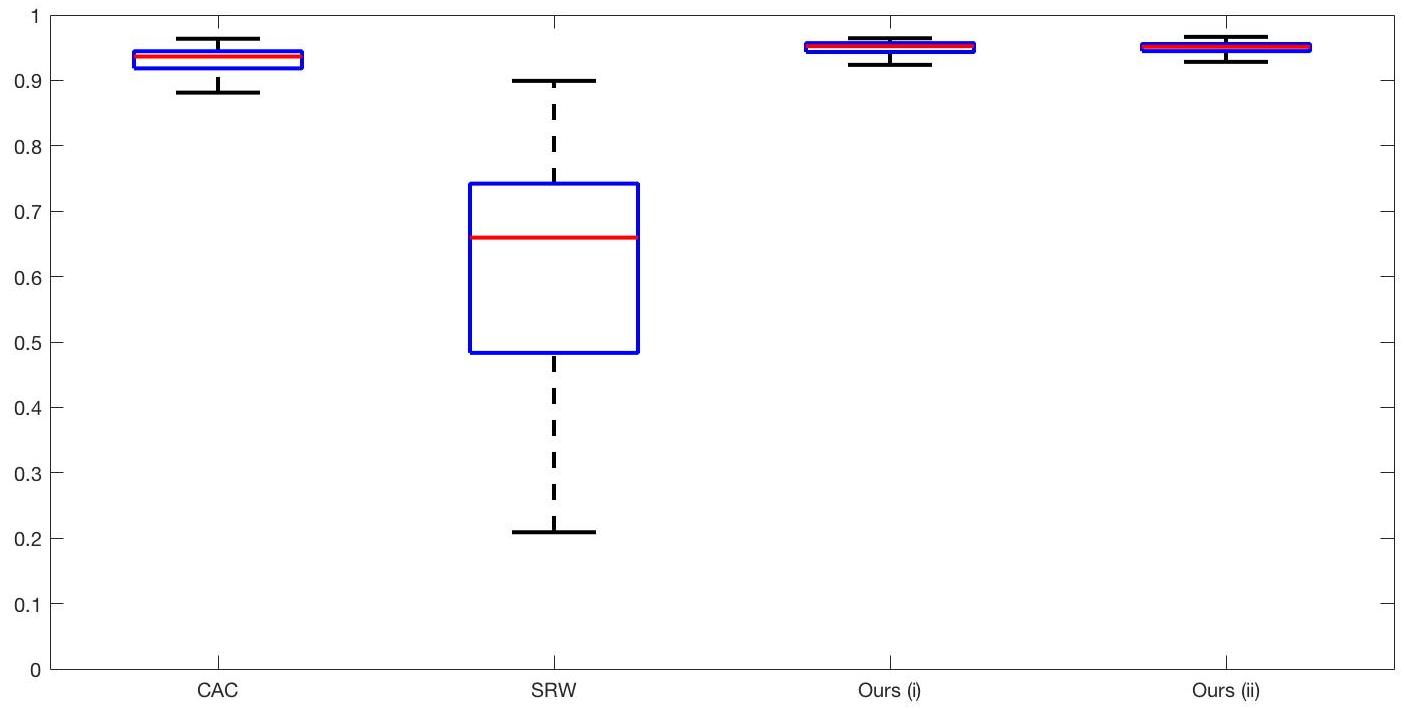

7.4 Alternative Selective Methods

In order to further establish the robustness of our method, we now introduce the results of testing our approach against competing interactive segmentation methods on a larger data set. The results are presented in Fig. 17, showing a boxplot of accuracy in terms of TC on a set of 30 CT images (excluding outliers). The target structure we consider is the spleen, as this consists of a relatively homogeneous foreground, appropriate for the approach considered. The data has been manually contoured providing ground truth data for the image set. We compare CAC Nguyen:12 and SRW SRW against our method with five variations of user input for each image. It is worth emphasising here that the input used in the tests is identical for each approach and was not refined in any way. It was designed to mimic what a user, unfamiliar with each approach, might select intuitively. A representative example for three images is shown in Fig. 18. This shows foreground (red) and background (blue) user input regions. For our method, we define the red region as as discussed in §1 and enforce hard constraints on the blue region. We refer to the results of the proposed approach using this input as Ours (i). We also include results of randomising the user input in an identical way to §7.3. For each image we generate 1000 simulated user input choices, which we present as Ours (ii). It is important to note that the difference between Ours (i) and (ii) is only the definition of . The method and parameters are fixed between each.

The performance of CAC Nguyen:12 is very good, as shown in Fig. 17. We have included an additional figure to highlight the difference between CAC and Ours (i) and (ii) more precisely. This is shown in Fig. 19 (this is the same as Fig. 17 with TC restricted to [0.8,1]). Here we can see that the proposed approach has a slightly better median (0.96 compared to 0.94) and is generally more consistent than CAC. This is particularly evident when considering the worst TC results of CAC () against ours ().

In Fig. 17 it can be seen that our method exceeds the performance of SRW by a large margin (0.66 compared to 0.95). One possible reason for this is that the input used, as displayed in Fig. 18, is restricted to be as intuitive as possible. SRW is capable of achieving improved results with more elaborate foreground/background input. However, it is generally reliant on a trial and error approach which is not ideal in practice. This highlights an important advantage of our method. It is able to achieve a high standard of results with simple user input. This is reinforced by considering Ours (ii), where the results of 30000 random variations of the user input does not cause a drop off in accuracy compared to the 150 manual user input selections. Again, this can be seen more clearly in Fig. 19. In fact, the results for the proposed approach with the random input are slightly better than with the manual input. This underlines the robustness to user input in the model, which is a vital aspect of selective segmentation.